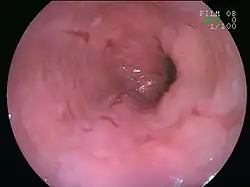

![]() | |

An esophageal ulcer visualized by esophagoscopy: the reddened area at 10 o'clock on the surface of the mucosa. | |